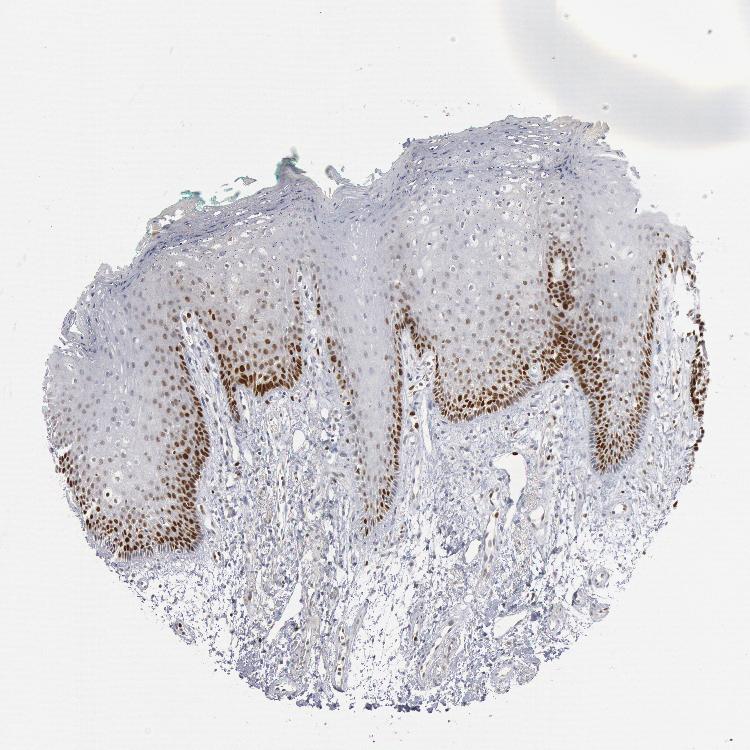

TISSUE PRIMARY DATA ORAL MUCOSA Show tissue menu

ORAL MUCOSA - Antibody stainingi

Antibody staining in the annotated cell types in the current human tissue is reported as not detected, low, medium, or high, based on conventional immunohistochemistry profiling in selected tissues. This score is based on the combination of the staining intensity and fraction of stained cells.

Each image is clickable and will lead to virtual microscopy that enables deeper exploration of all samples and also displays staining intensity scores, fraction scores and subcellular localization as well as patient and tissue information for each sample.

Antibody HPA001122

Squamous epithelial cells Medium